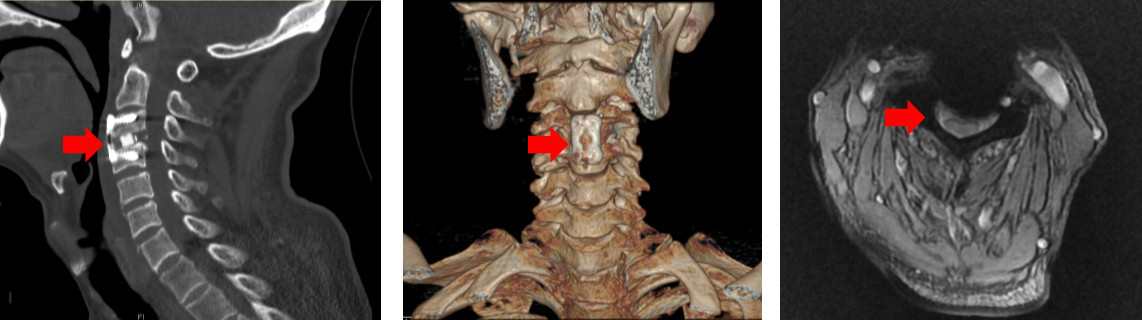

接诊金爷爷一家的是神经外科张培海医师,经过仔细询问病史和详细的体格检查,张医生发现病人神清语利,却出现了四肢的肌肉无力疼痛,高度怀疑金爷爷头部摔伤后暴力传导至了颈椎,导致“急性高位颈髓损伤”,随即为病人安排了颈椎CT检查。果不其然,金爷爷颈椎CT提示颈椎第3节滑脱,骨赘增生明显,颈椎管狭窄,脊髓严重受压。

图1 CT提示颈3椎体滑脱,颈椎管狭窄,脊髓严重受压